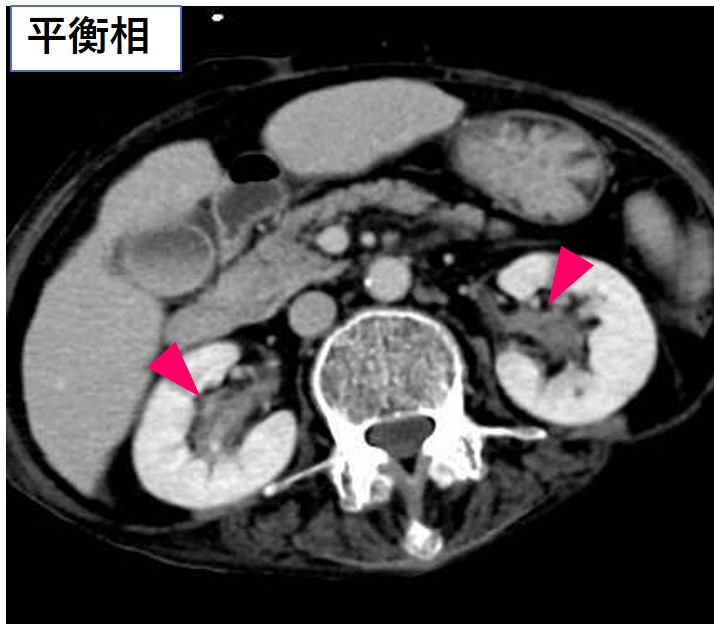

腹部造影CT(平衡相)

両側腎盂に壁肥厚を認める。

• Hairy kidney(68%)